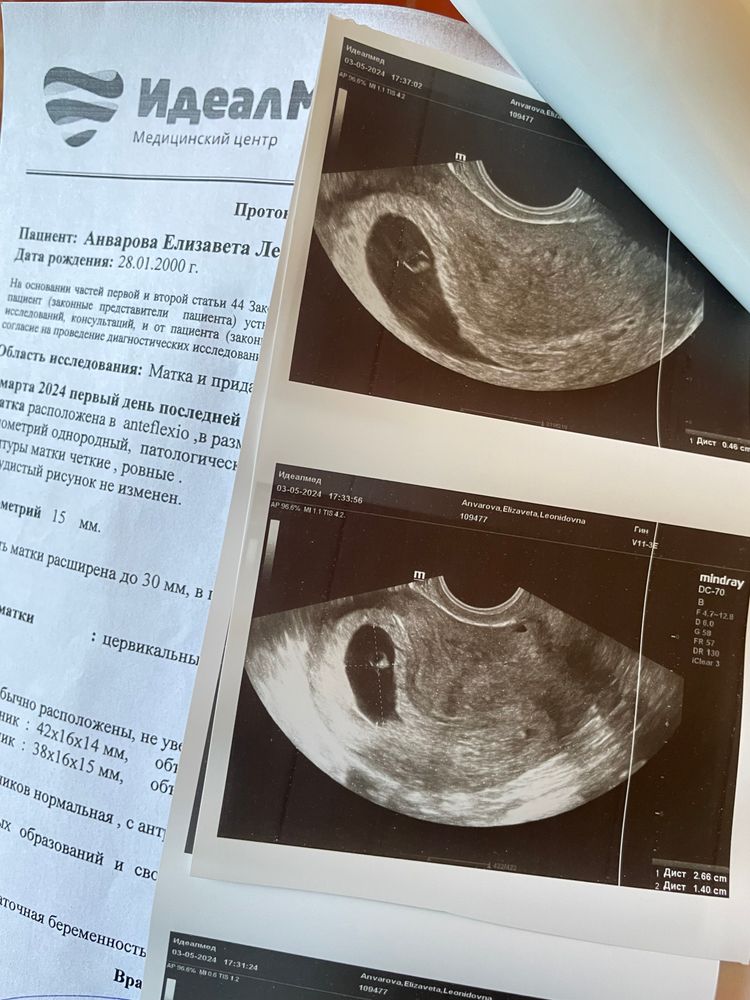

У меня в эту Б срок был по мес 8 недель, а на узи пошла там около 5 неделек всего было.

Мила Домогашева, вот у меня тоже самое,по мес 8 недель сейчас,но на узи ничего не сказали какой срок реальный(

Лиза Анварова, тоже примерно 5 недель , у меня так же только желточный мешочек был и все, даже второй еще не появился))ну вообще странный узист что замеры не сделал, мне сразу намерили 5 недель и сказали придти через 2 недели, там то мы и увидели 2 их малышей)) так что ждите, но хгч сдайте в динамике))

У вас получается 8 недель ставят по акушерскому сроку, я так понимаю. А эмбриональный он меньше еще, то есть у вас если поздняя овуляция и цикл так прыгает, то сейчас у вас по узи около 6 недель! До 7/7,5 недель эмбриональных сердце должно уже забиться. Значит вам пока паниковать еще рано. Вам просто по УЗИ срок неправильный поставили! Вам надо переделать УЗИ и идти к хорошему гинекологу!